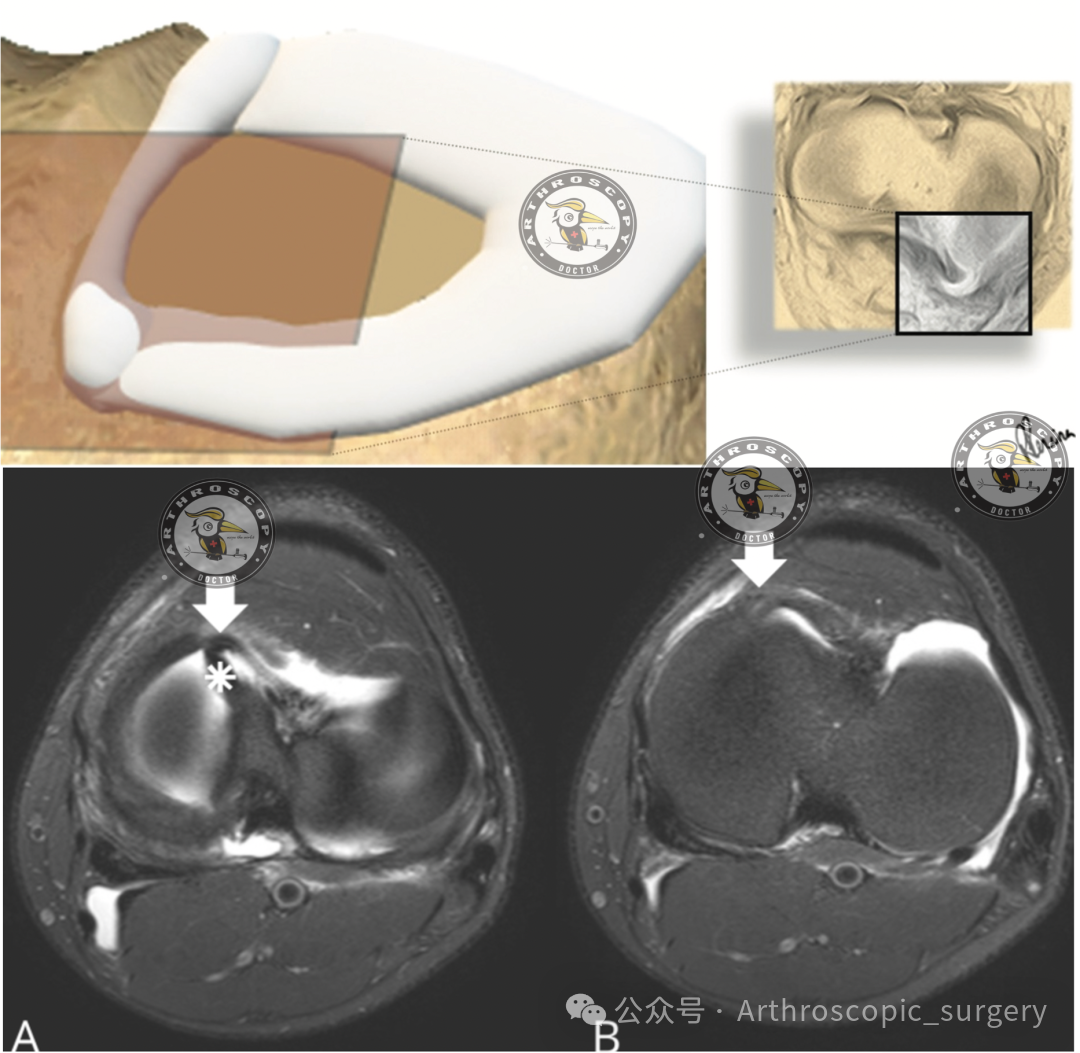

水牛角征

除了上述经典征象,Arth君今天要特别介绍一种在横断面图像上的新发现——水牛角征(Buffalo Horn Sign)。

具体表现为:内侧半月板在内侧胫骨平台前缘突出的低信号区域,形似一只“角”。外侧半月板在连续两层横断面图像上,表现为与外侧胫骨平台前缘平行的低信号角状带。

这个征象是由于移位的半月板“柄”部被横断面切面切到而形成的。研究显示,它的敏感度约为46.4%,是继髁间窝片段征和领结征消失之后的第三大常见征象。

因为它非常容易识别,且具有高度特异性——在正常的半月板中从未发现过此征象。识别它对于制定手术计划、决定是否进行半月板修复至关重要。